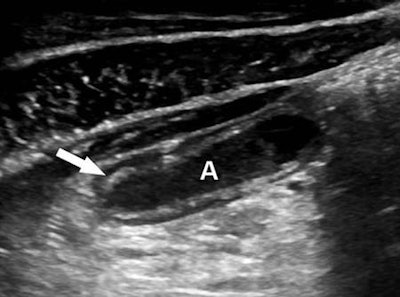

- Loss of the submucosal layer: Defined as either focal or global lack of visualization of the normally echogenic layer, confirmed in both the long- and short-axis views of the appendix

The researchers compared those results with the presence or absence of complicated versus uncomplicated appendicitis as determined histopathologically. Of the 119 patients, 32 (26.9%) had complicated appendicitis; 21 had gangrenous appendicitis and perforation, while 11 had gangrenous appendicitis without perforation.

After performing multivariate regression analysis, the researchers found that the loss of the submucosal layer was the only independent, statistically significant (p < 0.001) sonographic indicator of complicated appendicitis, yielding 100% sensitivity (95% confidence interval: 89.1%-100%) and 92% specificity (95% confidence interval: 84.1%-96.7%).